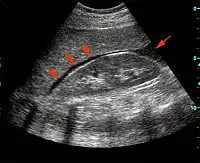

Focused assessment with sonography in trauma (commonly abbreviated as FAST) is a rapid bedside ultrasound examination performed by surgeons, emergency physicians, and paramedics as a screening test for blood around the heart (pericardial effusion) or abdominal organs (hemoperitoneum) after trauma.[1]

The four classic areas that are examined for free fluid are the perihepatic space (including Morison's pouch or the hepatorenal recess), perisplenic space, pericardium, and the pelvis. With this technique it is possible to identify the presence of intraperitoneal or pericardial free fluid. In the context of traumatic injury, this fluid will usually be due to bleeding.

FAST is most useful in trauma patients who are hemodynamically unstable. A positive FAST result is defined as the appearance of a dark ("anechoic") strip in the dependent areas of the peritoneum. In the right upper quadrant this typically appears in Morison's Pouch (between the liver and kidney). This location is most useful as it is the place where fluid will collect with a supine patient. In the left upper quadrant, blood may collect anywhere around the spleen (perisplenic space). In the pelvis, blood generally pools behind the bladder (in the rectovesicular space). A positive result suggests hemoperitoneum; often CT scan will be performed if the patient is stable[18] or a laparotomy if unstable. In those with a negative FAST result, a search for extra-abdominal sources of bleeding may still need to be performed.